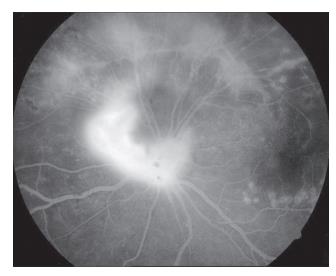

20230106112837_6460.jpg

图5 左眼眼底荧光血管造影检查见左眼视盘荧光渗漏,颞上视网膜大片无灌注区(发病36 d)

Figure 5 Fluorescein fundus angiography of the left eye showed high fluorescence of the optic disc,non-perfusion area of the supratemporal retina (oneset of 36 d)